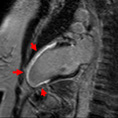

Seeing a Heart Attack. We can visualize heart attacks as bright areas after MRI contrast is given (see red arrows). Approximately, 13% of heart attacks go undetected by standard imaging exams.

Inflammation of the Heart. Not only can MRI visualize heart attacks it can also diagnose other causes of depressed cardiac function such as inflammation or fibrosis of the heart. The red arrows show areas of heart inflammation or myocarditis. No other cardiac test can detect this problem.